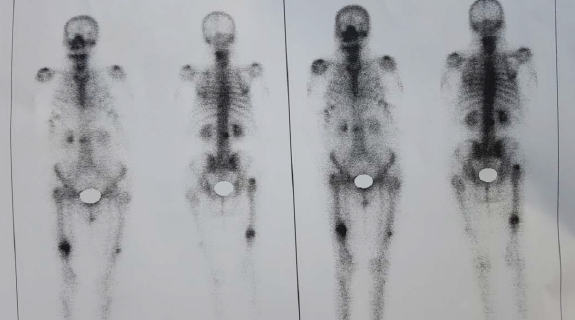

Una típica fractura bilateral de fémur: Presentación de caso.